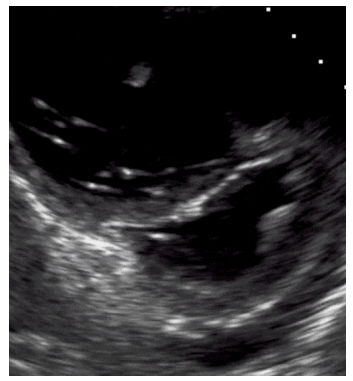

Paciente de 47 anos de idade, previamente hígido, internado na enfermaria de clínica médica devido à erisipela em membro inferior direito, inicia, no quinto dia de internação, dispneia e tosse. A equipe realiza USG à beira leito, que evidencia:

• Padrão A em todo hemitórax direito e esquerdo

• Veia cava turgida

• Ausência de derrame pericárdico

• Sinal de McConnel na janela apical 4 câmaras

• E seguinte imagem na janela paraesternal eixo curto

Legenda: D Sign

Com base nessa situação hipotética, assinale a alternativa com o diagnóstico mais provável.